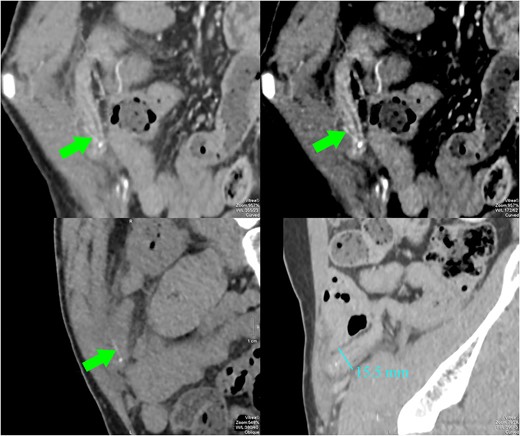

CT images showed a dilated appendix (maximum diameter 15.5 mm) with thickened and hyperenhancing wall. A small amount of free fluid and fat stranding was seen in the right iliac fossa. There was a linear hyperdensity measuring 13 mm (arrows) perforating and extending slightly beyond the appendix. No abscess or free gas collection was detected.